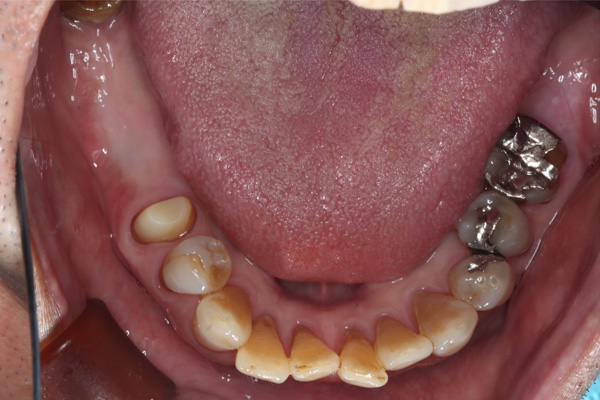

| 年代・性別 | 50代 男性 |

|---|---|

| 主訴 | 右下の歯がないのでインプラントをして欲しい |

| 治療期間 | 約6ヶ月 |

| 費用 | 600,000円 |

| 治療内容 | インプラント、骨造成、結合組織移植、セラミック修復 |

| 治療に伴うリスク | インプラント周囲炎 セラミックの破折、脱離 |

*キャンセルポリシーをご一読のうえご予約ください